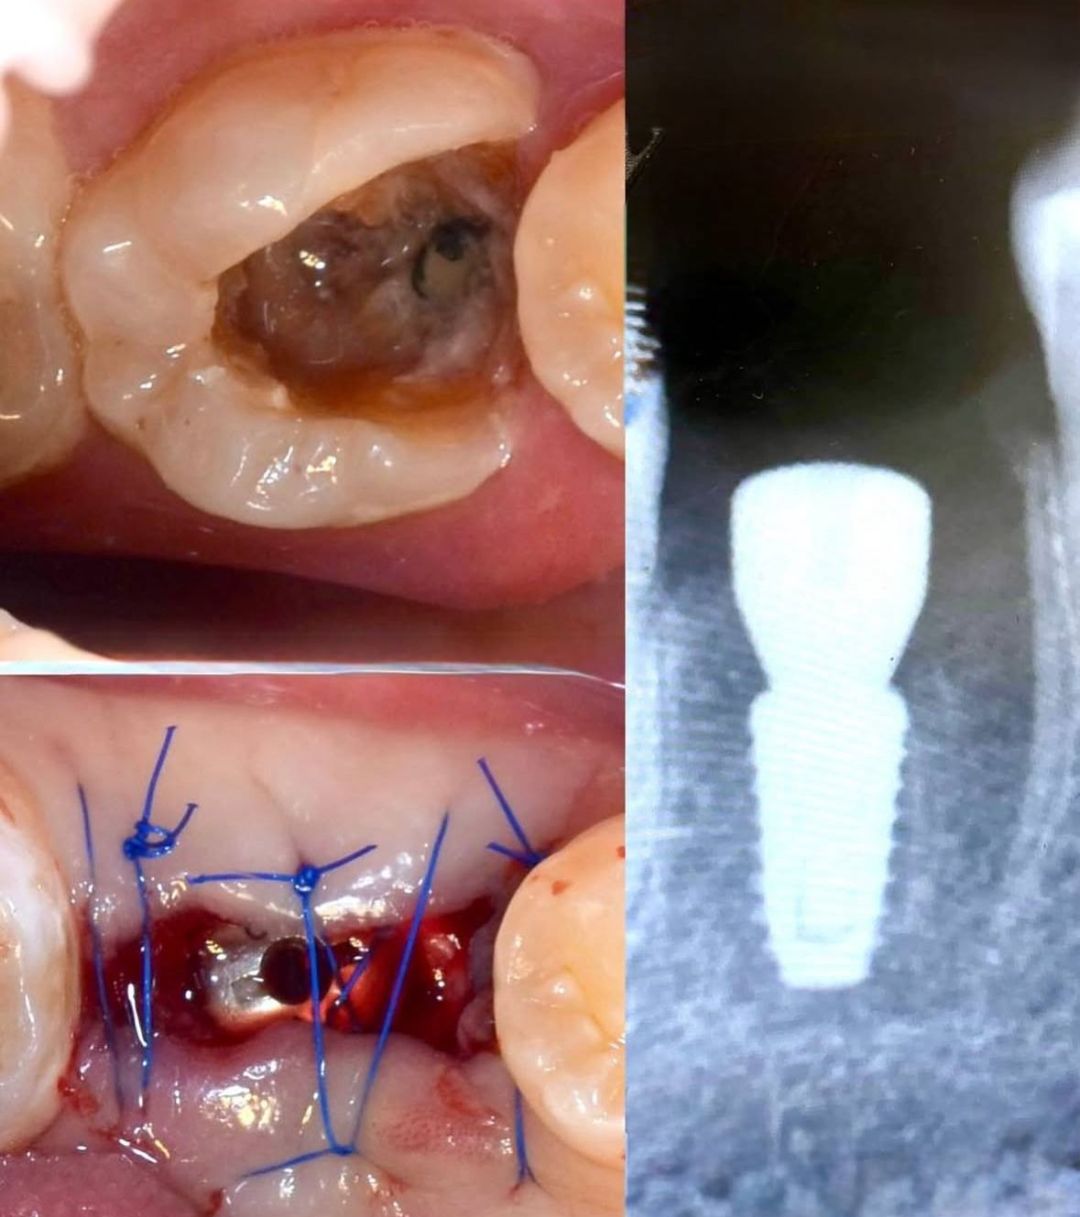

Примеры работ хирурга-стоматолога МИШИНА Е.О.

Фото работы

- Атравматическое удаление зубов, что позволяет провести дентальную имплантацию вместо удаленного зуба в день операции;

- Имплантация по классической методике.